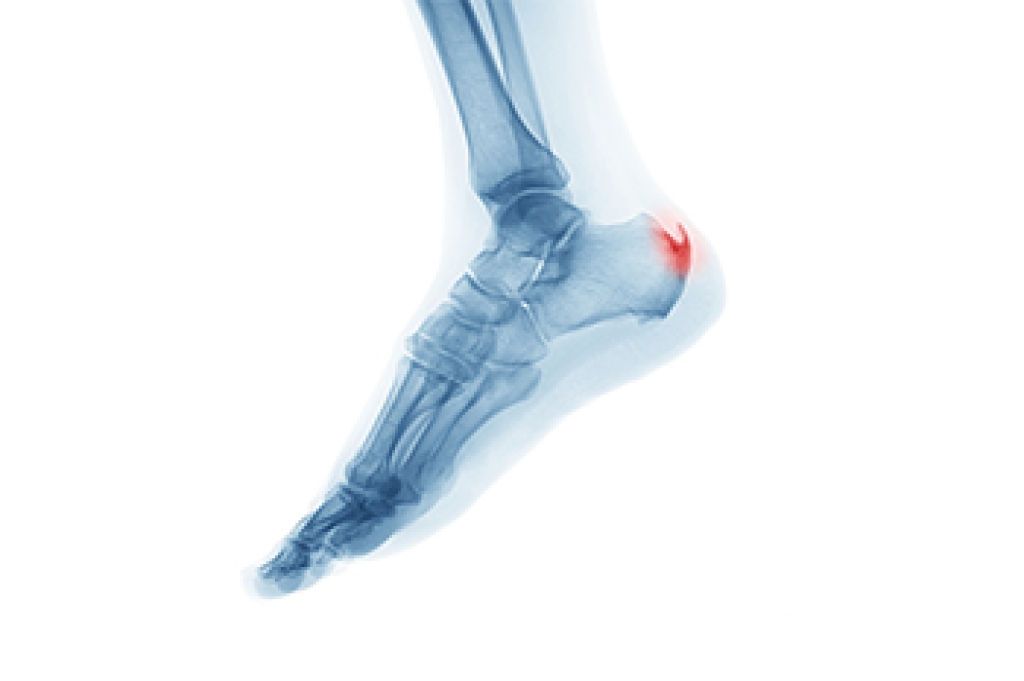

Tarsal tunnel syndrome is caused by compression of the posterior tibial nerve as it passes through a narrow space inside the ankle. This pressure can lead to tingling, burning, numbness, or shooting pain in the foot and ankle. Common causes include flat feet, swelling, injury, or underlying conditions that place stress on the nerve. Risk factors include repetitive activity, improper footwear, and prolonged standing. A podiatrist can perform a thorough evaluation, identify the source of nerve compression, and develop a personalized treatment plan. Options include orthotics, footwear guidance, or targeted therapies. Early diagnosis can prevent worsening symptoms and improve mobility. If you have any of the above symptoms, it is suggested that you consult a podiatrist who can accurately diagnose and treat what may be going on.

- Involves pressure or an injury, direct pressure on the tibial nerve for an extended period of time, sometimes caused by other body structures close by or near the knee.